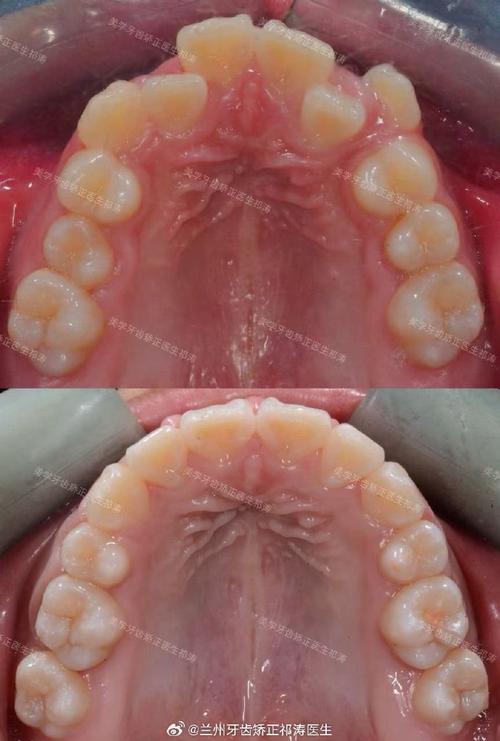

拔牙适应症主要分为三类:一是牙齿严重拥挤,表现为牙齿重叠、扭转,常规矫正无法排齐,需通过拔牙解除拥挤,为牙齿移动提供空间;二是牙齿前突(龅牙),上下牙弓前突明显,影响侧貌美观,拔牙可内收前牙,改善唇齿关系;三是咬合异常,如深覆合、深覆盖,需通过拔牙调整牙轴,建立稳定的咬合接触,临床中,最常拔除的为前磨牙(如上下颌第一或第二前磨牙),因其位于牙弓中段,拔除后既能提供足够空间,又不会影响前牙区和后牙区的功能。